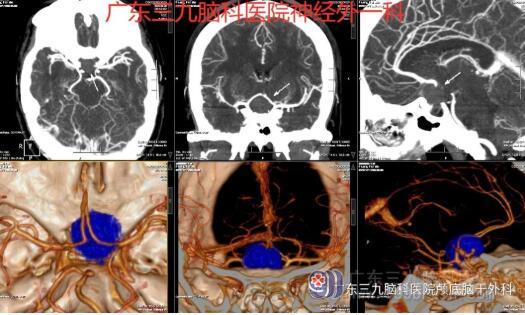

图1:术前头颅CTA检查示鞍上示一类圆形占位性病变,呈均匀高密度影,边界清晰,病变周缘示多发细小血管影,与双侧大脑前动脉A1段、右侧颈内动脉虹吸部关系密切,双侧大脑前动脉推压上抬。垂体明显变薄。双侧大脑前、大脑中及大脑后动脉主干及分支走行规则,未见狭窄、闭塞、畸形血管或局限性囊状增粗影。右侧大脑后动脉主要由后交通动脉供血。所及左侧椎动脉纤细。